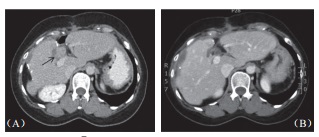

2位出现并发症病患均为乙肝患者,肝硬化B级,均有糖尿病病史,均为肝脏手术后复发病患,肿瘤一在第四段,大小为2.8cm,开腹下以4只探针进行治疗,一在第七段,大小为3.2cm,以5只探针进行经皮治疗。由于并发症数量太少以致难以分析,不过,可见病毒性肝硬化病患,具糖尿病病史,曾经手术切除后复发者,进行开腹式治疗,大肿瘤及使用多探针似乎较好发并发症。术后血液分析可见首日低度白血球上升,总胆红素值上升0.6 mg/dl (0.2~1.3mg/dl),AST 上升90IU/L(45~792IU/L),ALT上升122IU/L(59~875IU/L),alkaline phosphatase上升12IU/L(-2~145IU/L),肌肉酵素creatine kinase上升达140IU/L(12~210IU/L),但96.9%病患均在7日内恢复正常。其他术后心电图变化,肾脏功能指数或是尿液分析均为正常,一个月内影像上未见胆管受损迹(图2),也无肝脏缺血坏死区出现,但无肝内脓疡出现。

图2 62 岁男性肝癌病患在接受手术及射频消融后于总胆管及门脉旁复发,(A)3cm×2.8cm 大小肿瘤(箭头处)直接贴近肝门;B)消融后6个月肿瘤消失,消融区缩小明显,邻近胆管无扩张